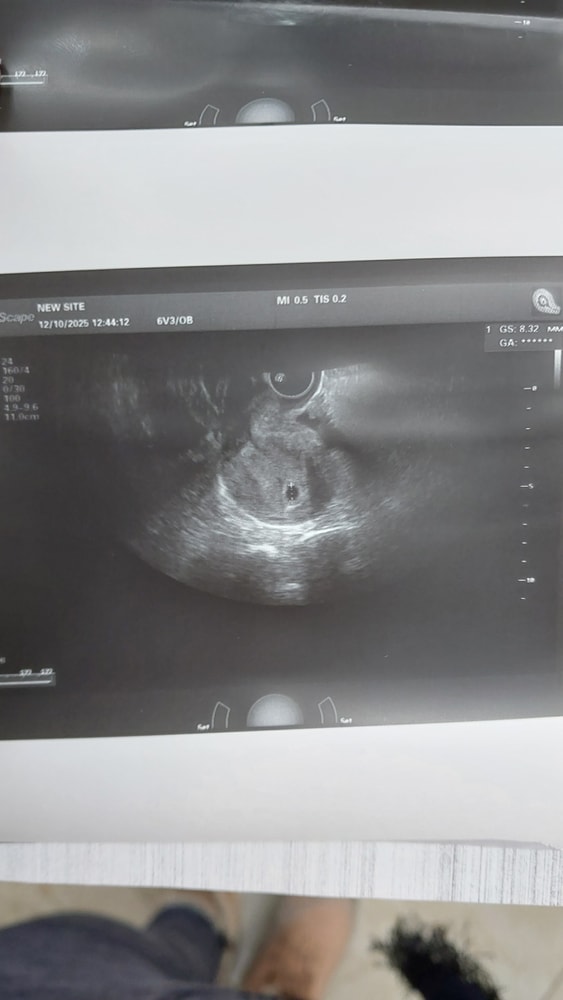

Ну ка ! Не двойня??😀

Малена , пока ПЯ одно, но бывает же и моно.... )))

А вам сказали размер ПЯ ?)

У вас какой срок?

Елена Мыльникова (кузнецова), по месячным 4недели+6дней